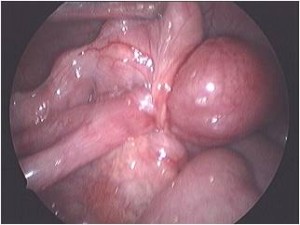

Most of the children with acute appendicitis require surgery. Surgery is commonly done by laparoscopy and the child is able to go home the very next day. ●

Ultrasound scan is a common and non invasive investigation which does not have any radiation exposure. It can pick up pathologies that are not visible on the outside or may not be apparent on clinical examination. One of the most common things that is picked up on ultrasound scan is enlarged mesenteric lymph nodes. The most common cause of this is intestinal infections or appendicitis. Rarely they can be due to tuberculosis or malignancy. In a well child, the size of these glands may be monitored by ultrasound scan on a monthly basis. If the size of the glands persist to 1.5 cm or larger and if there are multiple glands in the abdomen, a laparoscopic biopsy of the mesenteric lymph nodes may be helpful to arrive at a scientific diagnosis. ●